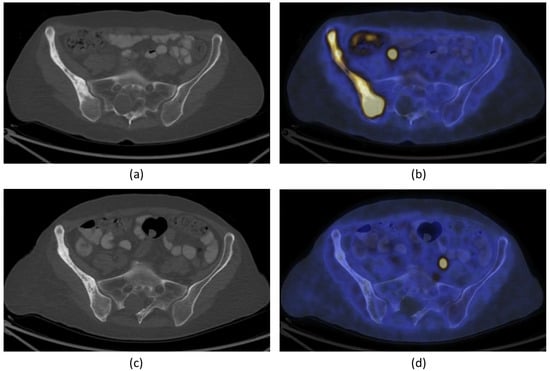

It was hypothesized that one of mechanisms of pain relief was ablation of the periosteal innervation causing a fast and enduring pain palliation. To address the above question, a detailed preclinical MR-HIFU study has been conducted in rats suffering from a painful prostate bone metastasis within the femur. Multimodal imaging and histological analysis demonstrated that pain control obtained after HIFU ablation was indeed associated with denervation of the periosteum (Figure 3) [29]. Besides managing pain, the same study demonstrated that HIFU provides local bone lesion control, where necrosis of tumor cells, inflammatory cells, osteoblasts, and osteoclasts were evident after MR-HIFU ablation (Figure 3) [29]. These preclinical results are consistent with outcome observed in multiple clinical studies [17,23,27,30,31]. Contrast-enhanced T1-weighted MR images showed an average decrease in enhancing tumor volume of 50.2% at 1 month after treatment compared with baseline, and 44% at 3-month compared with 1-month follow-up after MR-HIFU treatments. Additionally, in 56% of patients, CT images at 3 months revealed a bone density increase [17]. Napoli et al. evaluated tumor control in 18 patients using the MD Anderson criteria [30]. Results showed that at 3 months after MR-HIFU treatments, 11.1% of patients experienced complete response (CR), 22.2% of patients had partial response (PR), 55.6% of patients had stable disease (SD), and 11.1% patients had progressive disease (PD). CT images illustrated a bone density increase in combination with restoration of the cortical bone in 27.7% of patients with osteolytic lesions, a bone density decrease in 16.7% of patients with sclerotic lesions and no bone density changes in 55.6% of patients. Figure 4 shows examples of bone normalization after MR-HIFU treatments [30]. In a separate study, radiological response according to the MD Anderson criteria was observed in 9 out of 11 patients [27]. In addition, the World Health Organization (WHO) standard has also been used to investigate tumor response; in a study where 12 patients were treated with US-HIFU, the overall response rate was 75% where CR, PR, moderate response, SD, and PD were 41.7%, 43.3%, 8.3%, 8.3% and 8.3%, respectively [23]. Positron emission tomography (PET)/CT in combination with 18F-fluorodeoxiglucose (18F-FDG) is another imaging modality used to assess tumor metabolic response. At 4–6 weeks after US-HIFU, no abnormal accumulation of activity at tumor sites [23]. In a patient with mixed lytic-sclerotic lesion at the iliac bone, no FDG uptake was observed at 3 months after MR-HIFU treatment (Figure 5) [32]; meanwhile, in a separate case study involving an osteolytic lesion at the iliac bone, a 35.1% decrease in standard uptake value (SUV) was noted at 3 months after MR-HIFU treatment [21], confirming tumor response in both cases. Using the PET response criteria in solid tumors (PERCIST 1.0), another study reported PR in 5 out of 12 patients and SD in 2 out of 12 patients; 4 out of 12 patients had PD at a median follow-up of 90 days after MR-HIFU [27].